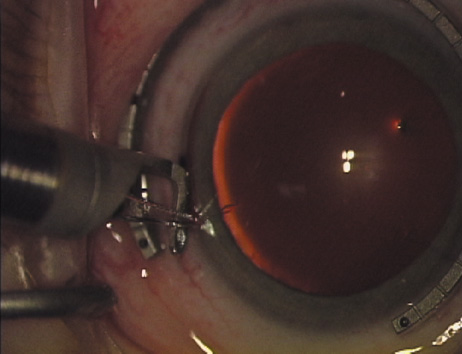

Case 1 is a 68-year-old male who presented for right cataract surgery. His refraction was −1.00 +2.25 × 80 and was recorded as reliable, consistent with his modest cataract density. Keratometry readings were 44.75 × 75 and 43.00 × 165. Corneal topography confirmed slightly more than 2.00 D of regular and slightly oblique cylinder. Consulting the nomogram, a plan was devised for a pair of LRIs to be centered over the 75-degree axis, with each incision delineating 45 degrees of arc. A single plane phaco incision was used and maintained at a size of less than 3.2 mm (Figs. 811).

Fig. 11. Opposite relaxing incision is completed. (Reprinted from Hardten DR, Lindstrom RL, Davis EA. Phakic Intraocular Lenses: Principles and Practice. Thorofare, NJ: SLACK Incorporated, 2004, with permission.)